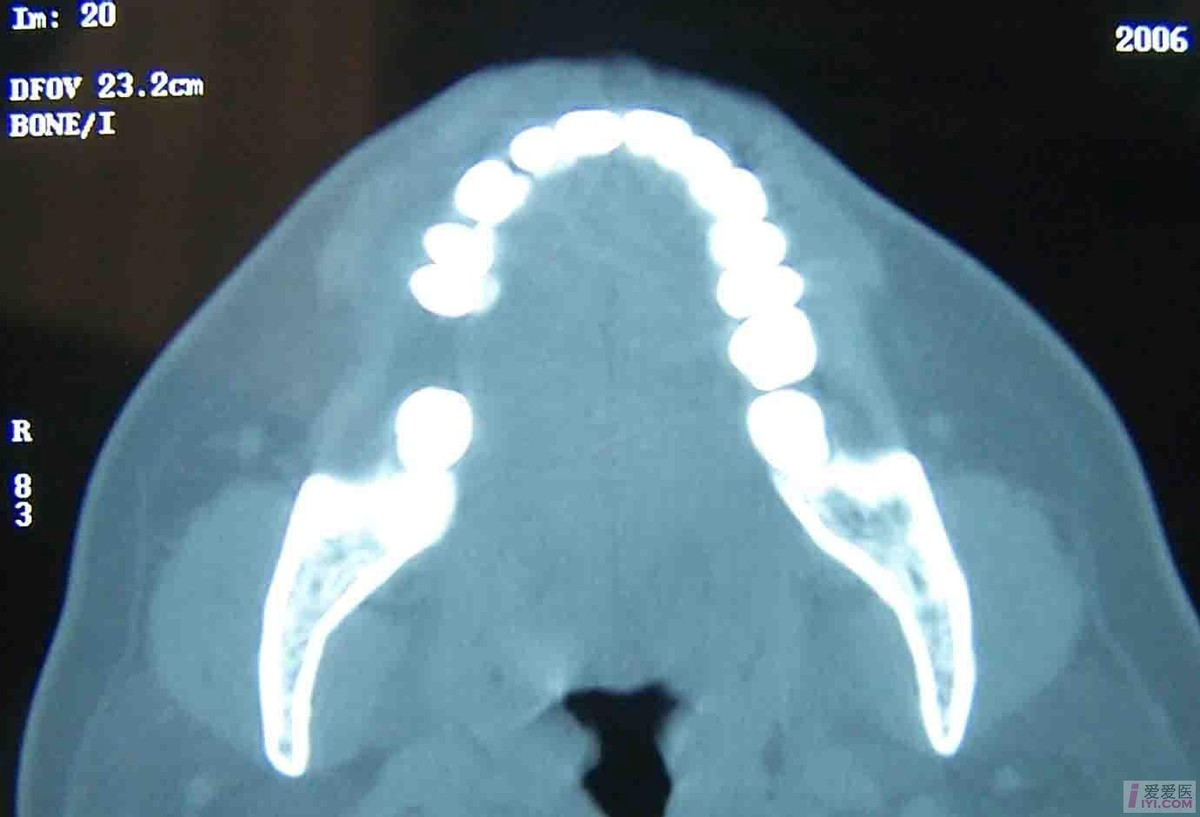

1.好发于下颌骨,特别是下颌磨牙区,于发病部位出现实质性肿块,生长迅速,扪诊无乒乓感,可有压痛。

有炎症病史,X线片可见骨质破坏及骨膜增生的修复性改变。临床和X线不能鉴别时,应在手术时作冰冻切片,以排除 中央性颌骨癌 。